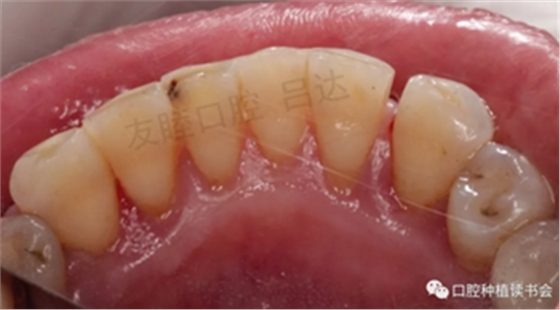

圖8 下頜前牙區(qū)

圖9 治療前牙周系統(tǒng)檢查表